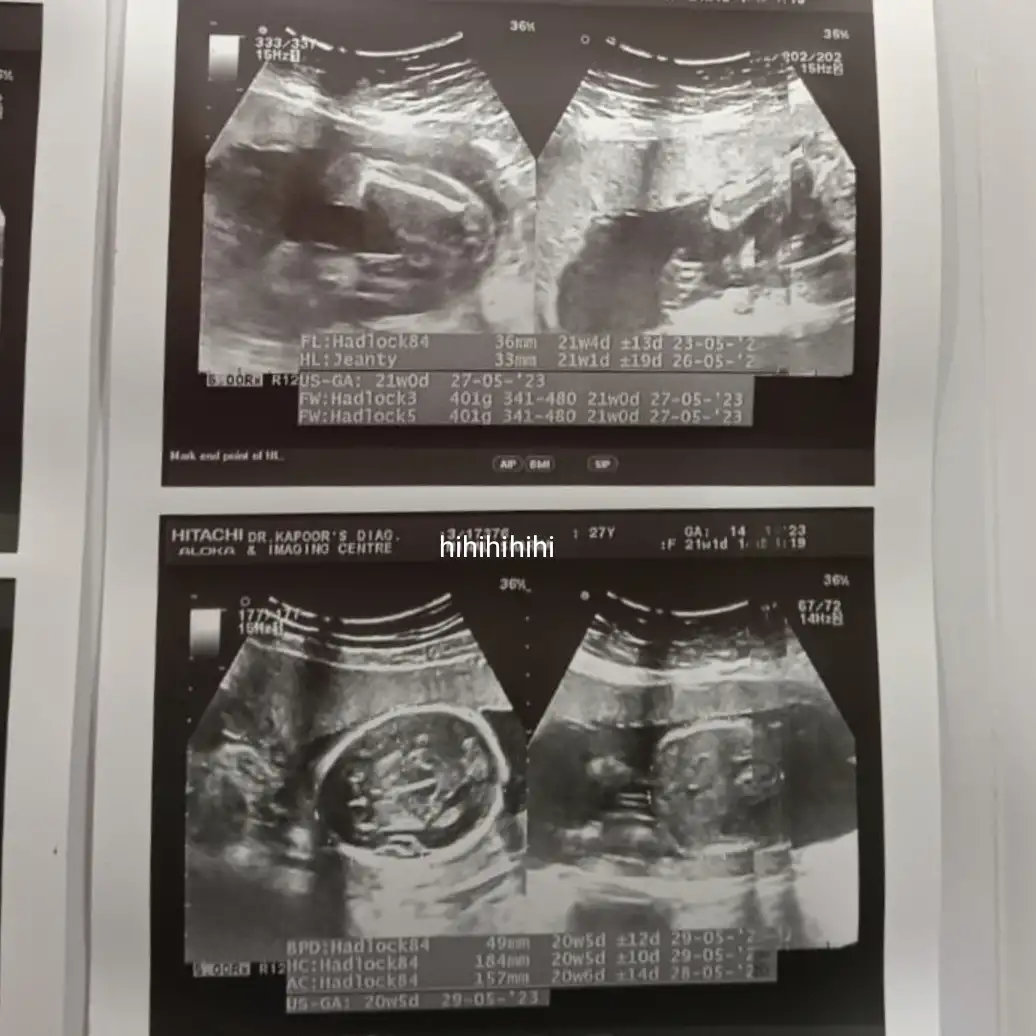

Q: Guess who is coming πŸ’œπŸ’™